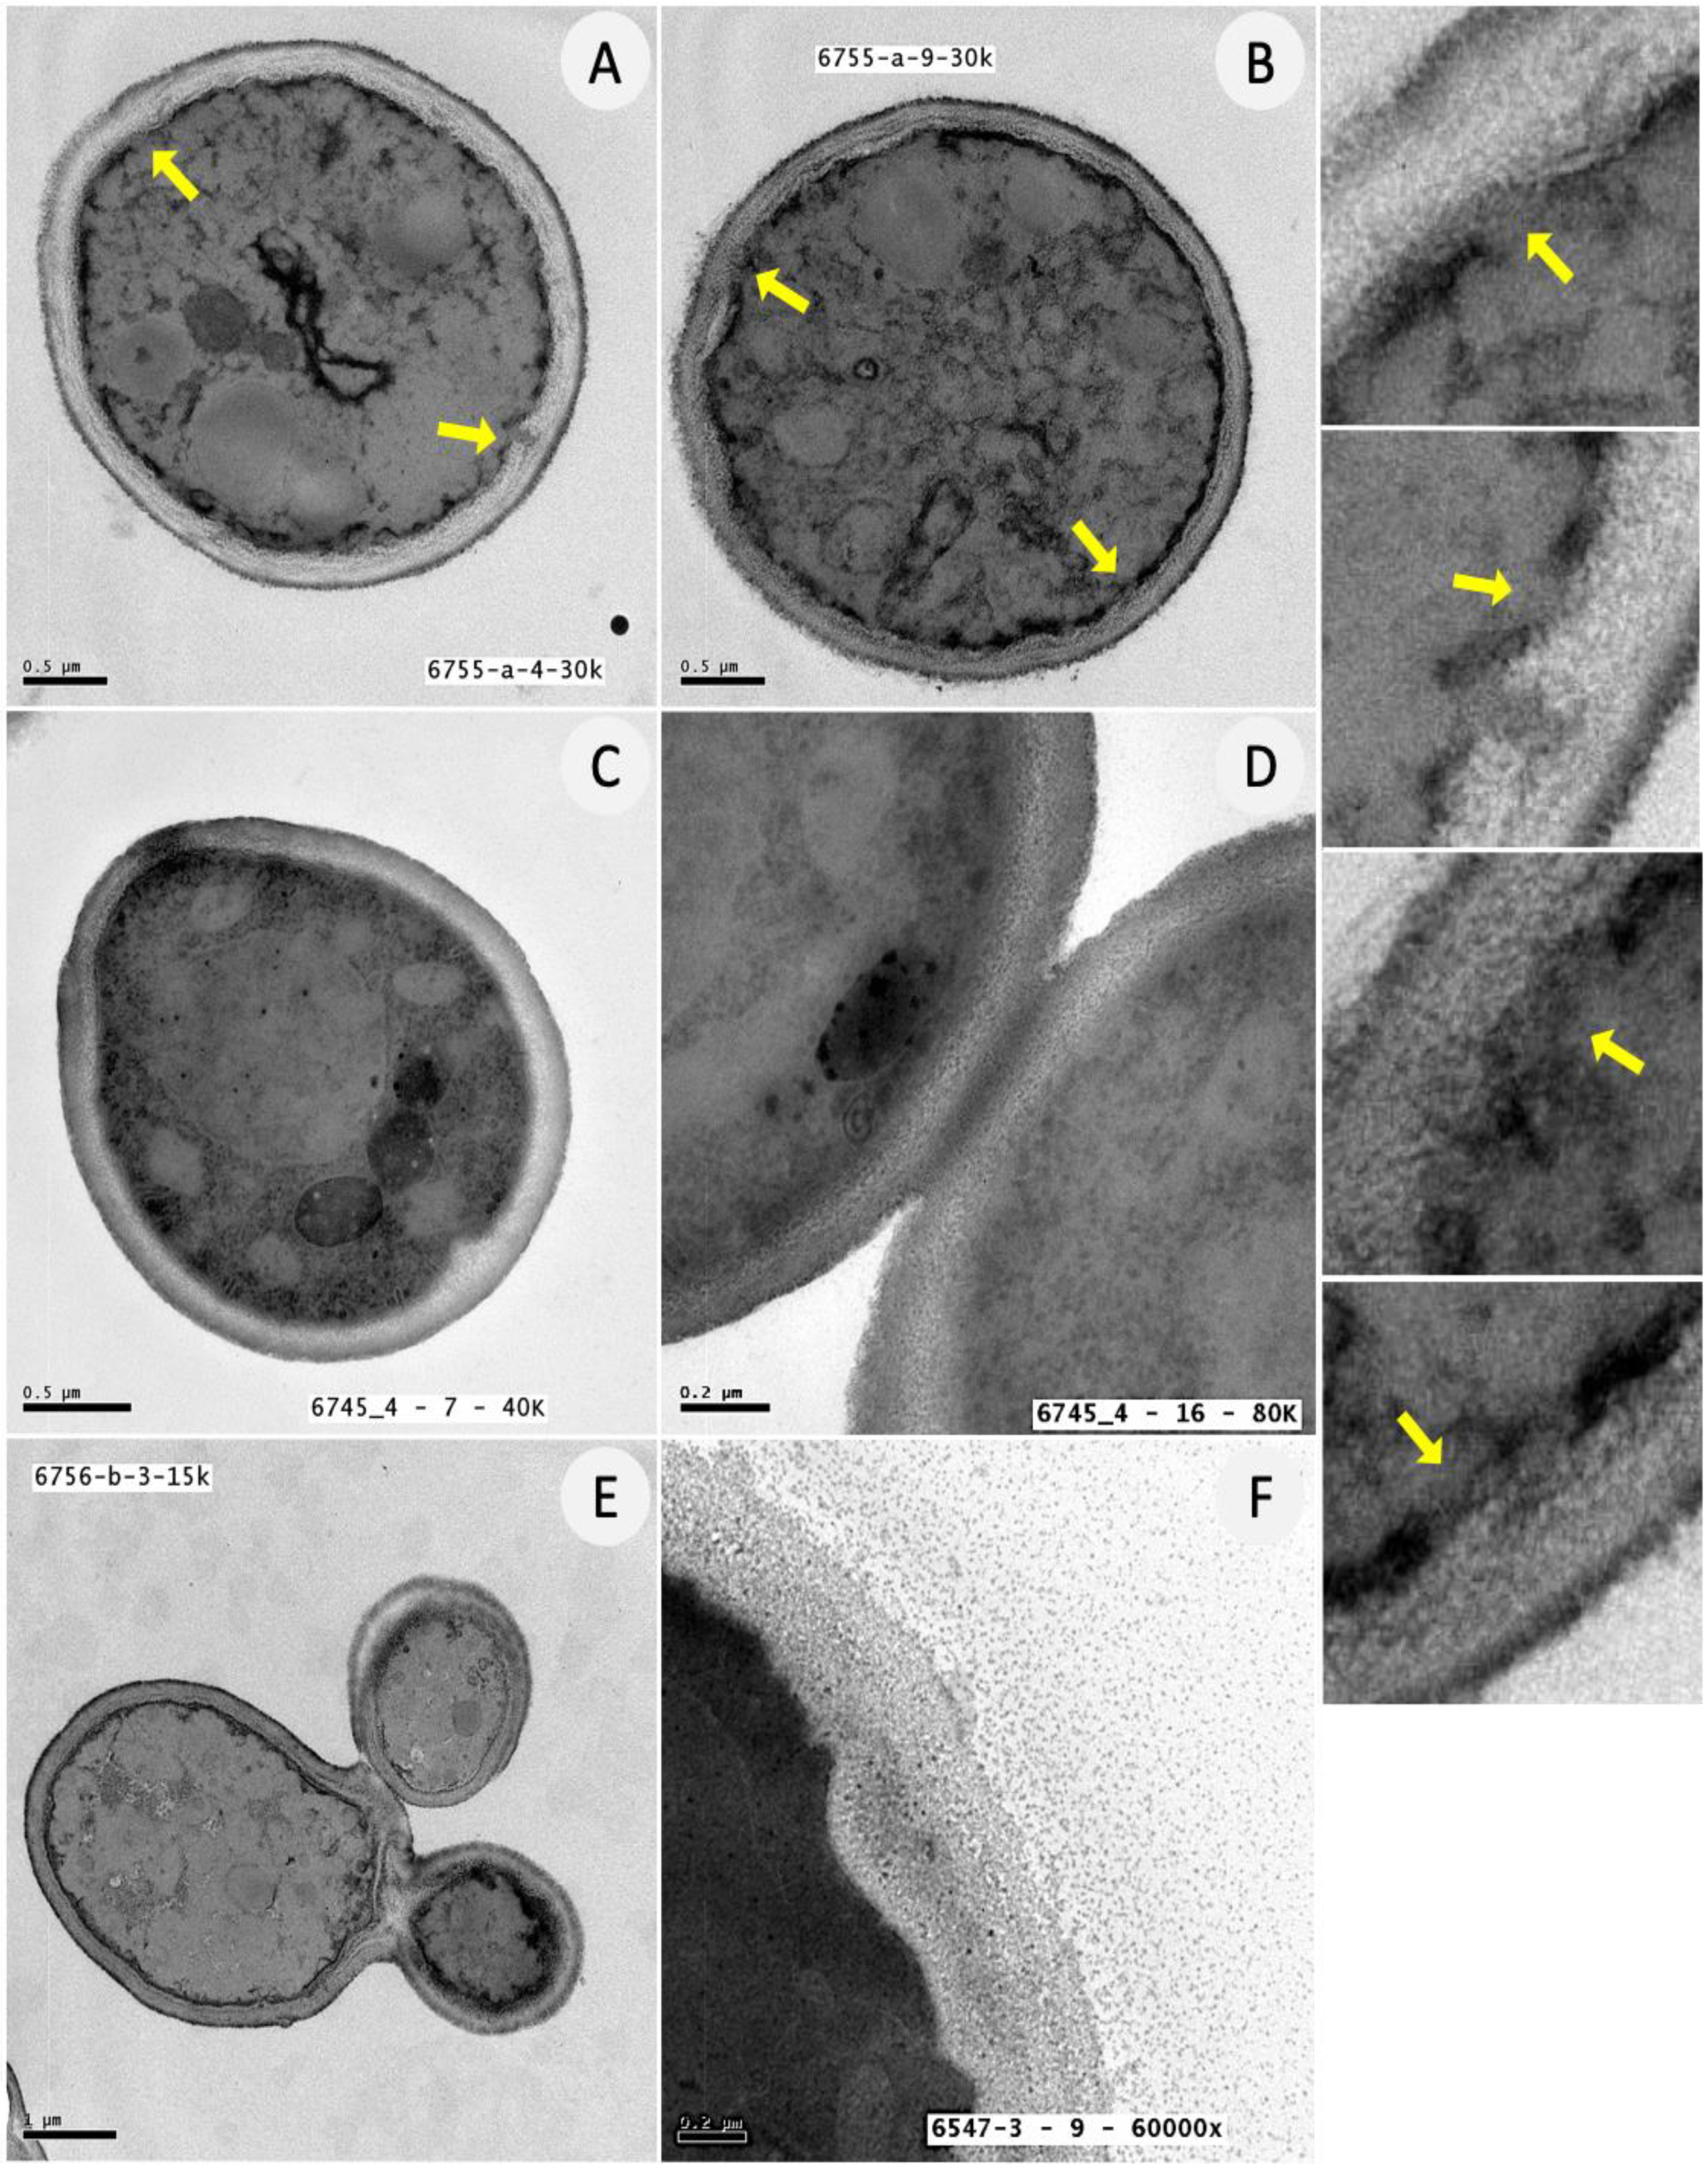

3.5. Ultrastructural Analysis of C. albicans Biofilm Cells upon Exposure to ATRA